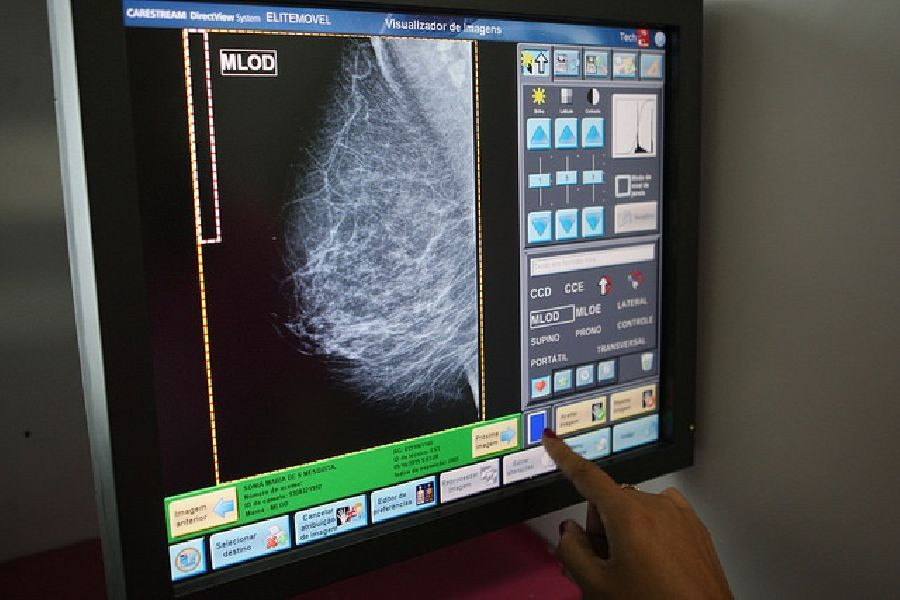

Una investigación internacional apunta a un nuevo tratamiento eficaz contra el cáncer de mama

Un estudio internacional dirigido por científicos de la Universidad de Sussex, en Reino Unido, ha proporcionado pruebas sólidas de un nuevo objetivo eficaz para el tratamiento del cáncer de mama.